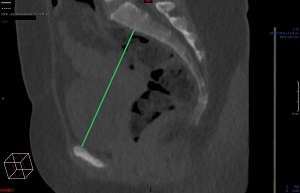

Tunna snitt-serien axialt i Power Viewern ("MPR"), snittjocklek 7-10 mm, skelettfönster. Scrolla fram till symfysens mitt. Mät det kortaste avståndet mellan symfysens kaudala-dorsala omfång och coccyxspetsen.